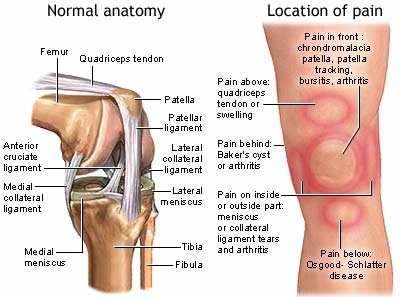

Gambar-gambar Penyebab Nyeri Lutut, Kenapa Knees Hurt - Sakit-Pengurusan - 2020

Gambar-gambar Penyebab Nyeri Lutut, Kenapa Knees Hurt - Sakit-Pengurusan - 2020

Menyadari Jenis Nyeri Lutut

Menyadari Jenis Nyeri Lutut